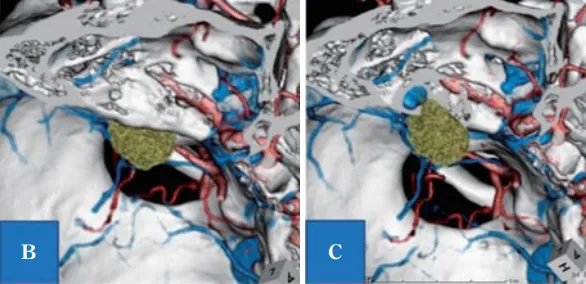

影像学检查结果

B:计算机断层扫描血管造影(CTA)显示,左上前象限存在肿瘤病灶(绿色区域为强化部位)

C:B图所示内耳道壁骨质缺损,显示高位颈静脉球极度贴近内耳道及肿瘤区域